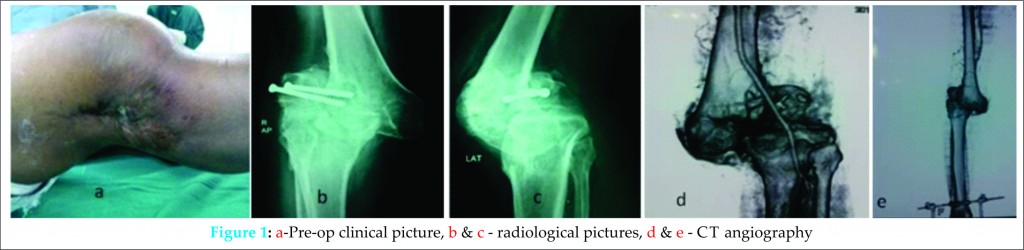

We report a 48 year male patient with a history of fracture lateral femoral condyle of right knee due to road traffic accident 10 years back, for which he had been operated with open reduction and internal fixation with cancellous screws, which subsequently got infected. He had repeated trauma to the limb two years post surgery and this time was treated conservatively in a plaster cast. For last eight years he had a downward spiral in knee function . On presentation to our clinic one year back, he had pain in the right knee, inability to bear weight and varus deformity along with discharging sinus (Fig-1a). He was barely able to take a few steps without support and had constant pain. On examination, the knee was swollen with mild effusion, skin was adherent to the bone with puckering, 20 degrees of varus deformity, gross medio-lateral instability and patella was fixed in the lateral gutter. The distal neuro vascular status was intact. On radiographic examination, the knee was postero-laterally sub-luxated (Fig1 b,c). CT angiography was done to chalk out the course of the popliteal vessels (Fig-1d,e).